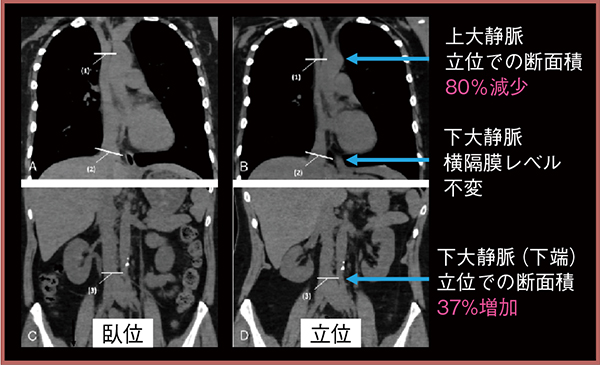

臥位に比べ,立位では上大静脈(SVC)の断面積の変化量は80%減少し,下大静脈(IVC)は横隔膜レベルでは不変だが,下端では37%増加するなど部位によっても異なる1)(図4)。しかし,心不全患者では立位でもSVCの減少が見られず,立位SVC断面積と心カテ右心房圧の良好な相関が示された。そのため,侵襲的な右心カテーテル検査が施行できない心不全患者などにおいては,立位撮影が血行動態の指標となり,心不全の重症度判定への応用の可能性が考えられる2)。

図4 立位撮影による上下大静脈の評価